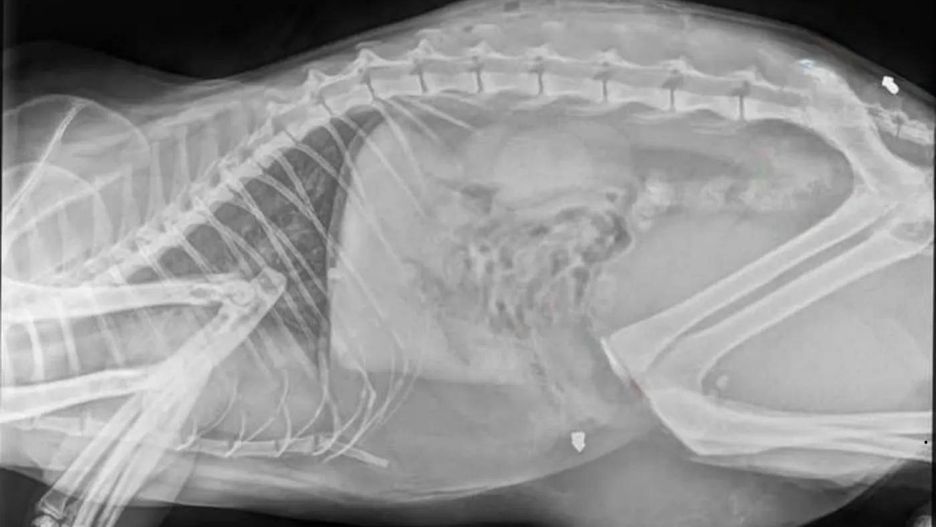

- W weekend nasz kot został kilkukrotnie postrzelony z wiatrówki. Grzybkowaty śrut jest w pobliżu kości krzyżowej oraz w otrzewnej. Poza tym ma jeszcze ranę na grzbiecie, najprawdopodobniej po nietrafionym strzale. Bardzo proszę o wiadomość jeśli ktokolwiek ma jakieś informacje w tej sprawie lub słyszał strzały w miniony weekend - opowiada w rozmowie z portalem gorzowianin.com pani Aleksandra, mieszkanka Kłodawy.

Sprawa została zgłoszona na policję. We środę 5 marca kot przeszedł operację pod narkozą. Na szczęście wszystko przebiegło pomyślnie i zwierzę przeżyło. Niestety nie jest to pierwszy tego typu przypadek w gminie Kłodawa. Dużo mniej szczęścia miał kot z Wojcieszyc, który w listopadzie 2024 roku został zastrzelony przy pomocy wiatrówki.